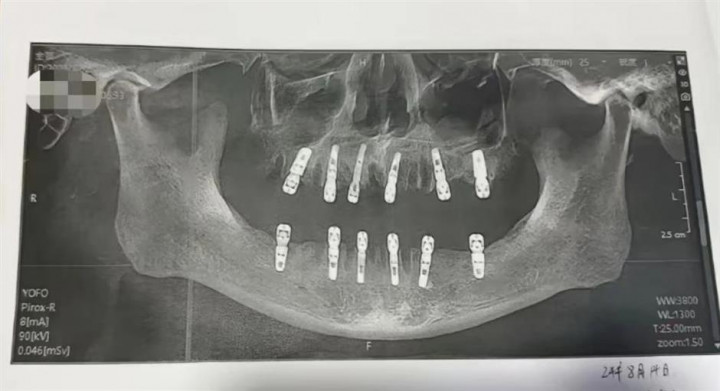

Pria di China Meninggal Dunia usai Cabut 23 Gigi dan Pasang 12 Implan Dalam Sehari